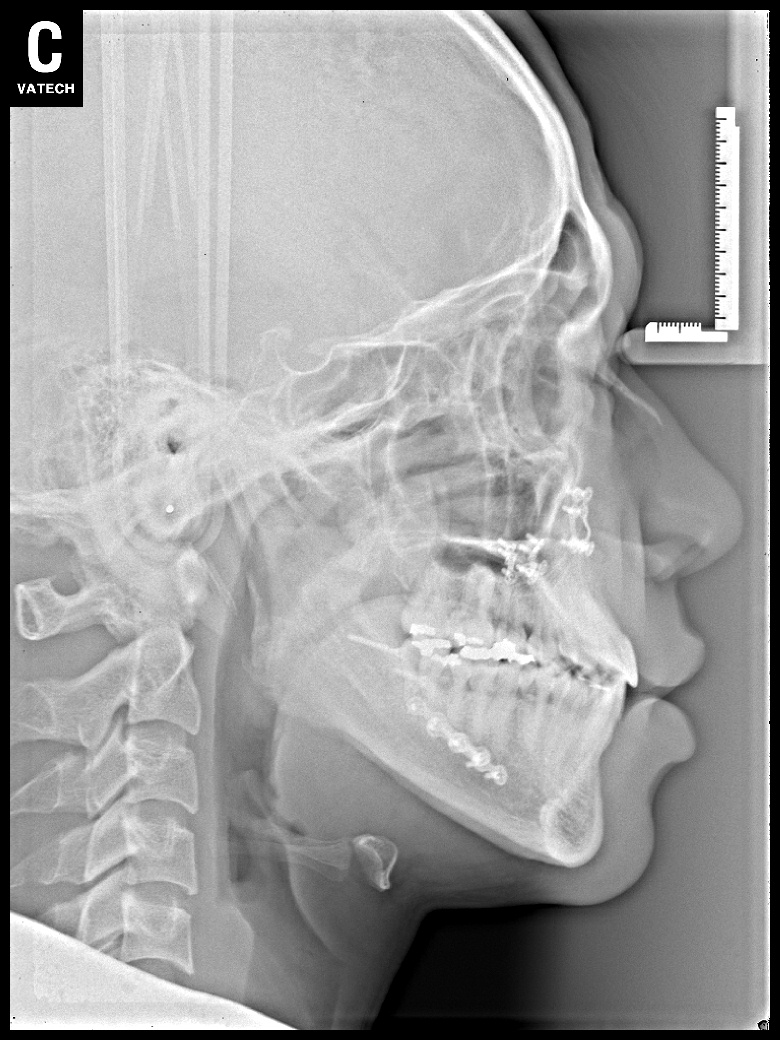

치료 후 사진입니다.